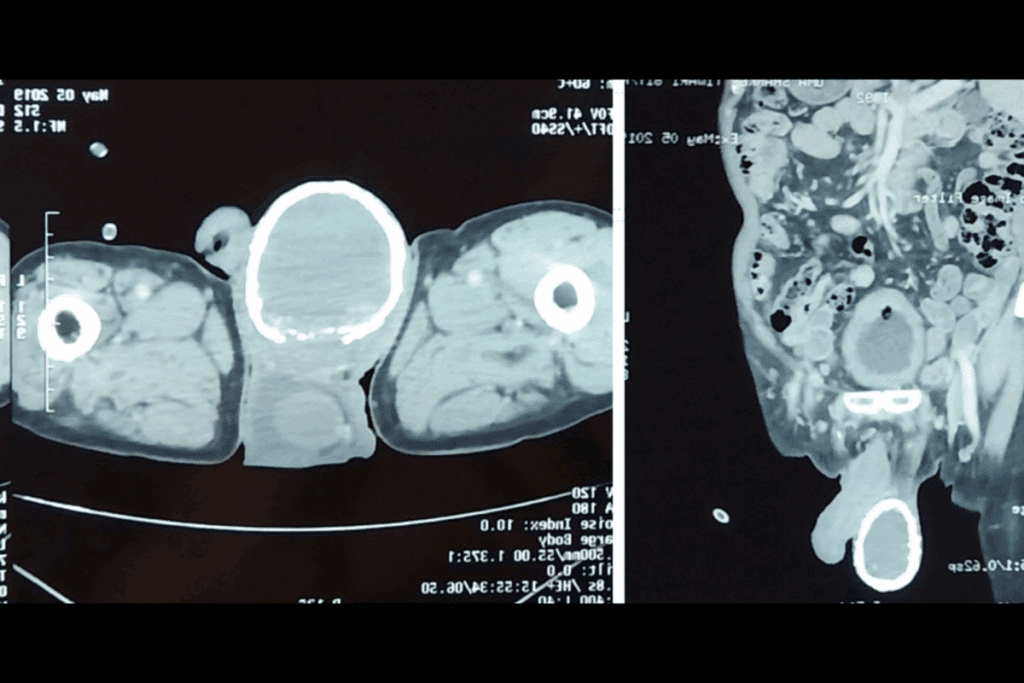

Imaging Requirements for EVT Candidacy

Imaging is key in deciding if someone can have EVT. Doctors use CT angiography (CTA) and MR angiography (MRA) to see the blocked blood vessel and how much brain tissue is at risk.

| CT | Assess early ischemic changes |

| CTA | Identify occlusion site and collateral circulation |

| MRI | Evaluate infarct core and penumbra |

A recent study found that new imaging methods have changed how doctors pick patients for EVT. Now, they can spot who will really benefit from the treatment more accurately.